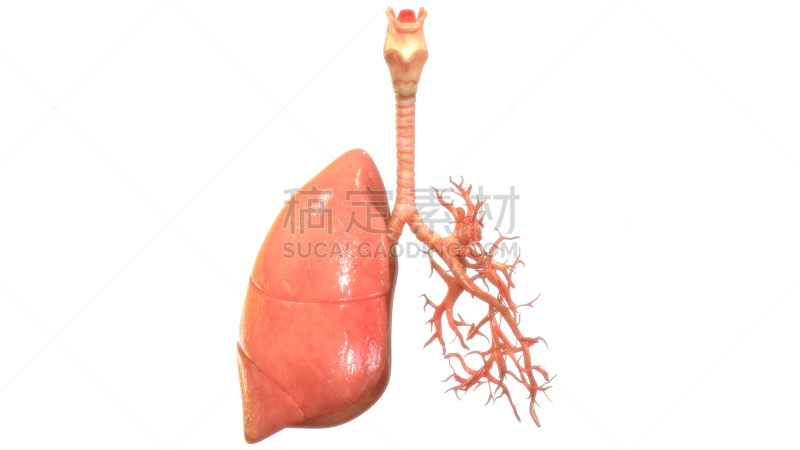

有细支气管的人的肺详情

JPG